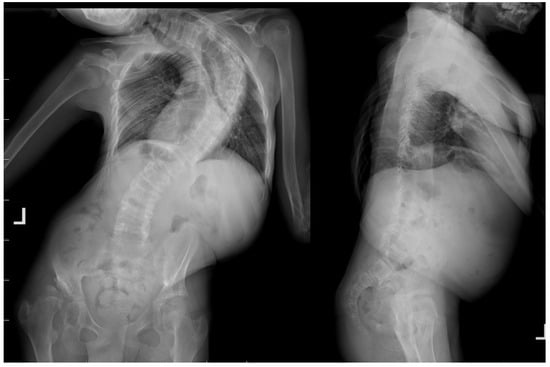

Figure 2.

Radiological standing X-rays AP and LAT of 14-year-old immature patient with Costello syndrome, severe spinal deformity measured of 130 degrees.

A 14-year-old boy was admitted to our clinic due to rapidly progressing scoliosis. He had previously been treated by other physicians and had an extensive history of conservative treatment of spinal deformities, including the use of a Cheneaux brace. Despite all the efforts made, the scoliosis continued to progress. During a visit to our clinic and examination, we revealed a spine curvature of 130 degrees (Figure 1 and Figure 2). The boy used a wheelchair due to severe walking problems. He was able to walk about 50–100 m on his own, but he developed pain in his spine and the left hip joint, which was dislocated. Although the boy was 14 years old, his mental development could be estimated at the age of a seven-year-old child. Additionally, we diagnosed that both of his feet were deformed, flat-valgus, making walking difficult, and had not been treated so far. Contractures were also revealed in all joints of the upper and lower limbs, slightly limiting mobility. However, the biggest functional problem was severe scoliosis, which was stiff and correctable only in about 30 percent. We recommended tests to prepare for and qualify for spine surgery. Spinal MRI diagnosed Chiari II syndrome and syrinx (Figure 3). This patient underwent foramen magnum decompression 3 months before planned surgical correction for severe scoliosis. Then, due to severe scoliosis of 130 degrees, bone immaturity and insufficient T1–T12 dimensions, the patient was qualified for surgical treatment using magnetically controlled growing rods (MCGR), due to surgical technique described in the literature [,,]. Other less invasive techniques for traction spinal deformities [,,,], such as halo gravity traction (HGT), could not be used due to the fact that HGT treatment is contraindicated in the presence of spinal pathologies such as syrinx, spinal tumors, increasing the risk of neurological complications during HGT course. Also, instability of the spine in the occipital–cervical and cervical region disqualifies the patient from such treatment. In our case, the patient underwent Chiari II syndrome decompression and had syrinx. For this reason, we considered MCGR treatment to be the least invasive [,]. We did not consider anterior release because it is a rather antiquated technique and the superiority of other methods of surgical treatment without disturbing the continuity of the chest has been proven [,,,,,]. This solution was very good for the patient because our surgical technique provided minimal surgical technique, implantation of screws and rods through two small incisions, and correction by distraction under the control of spinal cord neuromonitoring (Figure 4) []. In the period after MCGR implantation and subsequent spine surgery, pediatric orthopedists performed two foot deformation correction surgeries (Figure 5). After spine surgery using MCGR, we gradually performed MCGR distraction over the next 2 years, and after no further distractions were possible, we performed the final surgery, conversion to PSF with simultaneous multi-level Ponte osteotomy, which gave a very good and satisfactory surgical result []. In the perioperative period, two serious complications occurred: pneumothorax caused by central catheter, and gastrointestinal bleeding due to previously undiagnosed gastrointestinal varices. Pneumothorax was treated with pleural drainage (3 days), and bleeding from the gastrointestinal tract was treated gastroscopically. Finally, the patient was placed in an upright position on the 4th postoperative day and left the hospital on the 8th postoperative day, with full satisfaction with the treatment. The patient was monitored on an outpatient basis every 3 months. After the surgery, his body’s performance improved significantly and his spine pain decreased. T1–T12 height and T1–S1 improved from 156 mm and 268 mm preoperatively, respectively, to 194 mm and 332 mm after MCGR placement, respectively, and 215 mm and 368 mm after definitive surgery and posterior final fusion. He can walk about 2 km a day without any pain (Figure 6 and Figure 7).